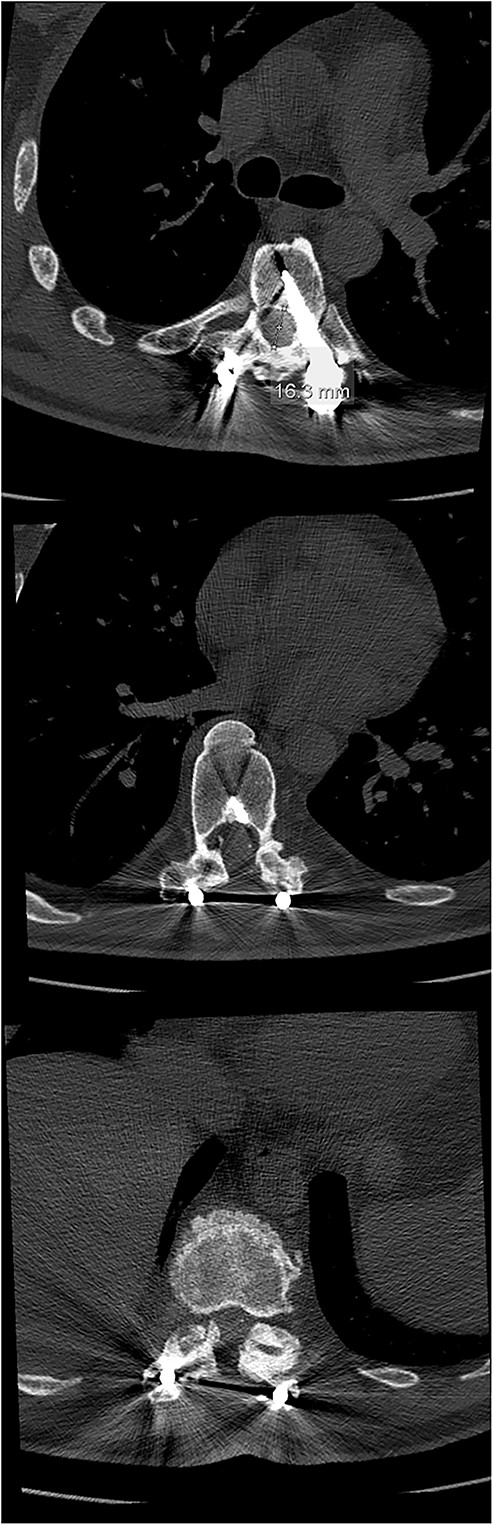

Six weeks after surgery he was transferred to a tertiary rehabilitation center, ambulating using a walker, but remained wheelchair-bound for longer distances. The postoperative pain was manageable with non-opioids. During the regular follow-ups, the paraplegia with severe spasticity persisted, without significant pain. A subsequent insertion of the intrathecal baclofen pump in a tertiary rehabilitation facility enabled the patient to manage the muscle spasms in his lower limbs, particularly during transfers from the wheelchair to bed and vice versa. The patient was able to urinate spontaneously with minimal urine retention, and no need for self-catheterisation, reporting satisfaction with the outcome of the surgery and rehabilitation, which enabled him a return to his workplace and retain a significant level of independence in everyday activities. On the final follow-up imaging, 4 years after the surgery, no significant deformity progression and no evidence of neurologic impairment were observed (Figs 4 and 5).

X-rays at the final follow-up 4 years after the surgery. Anteroposterior view (left) and lateral view (right).